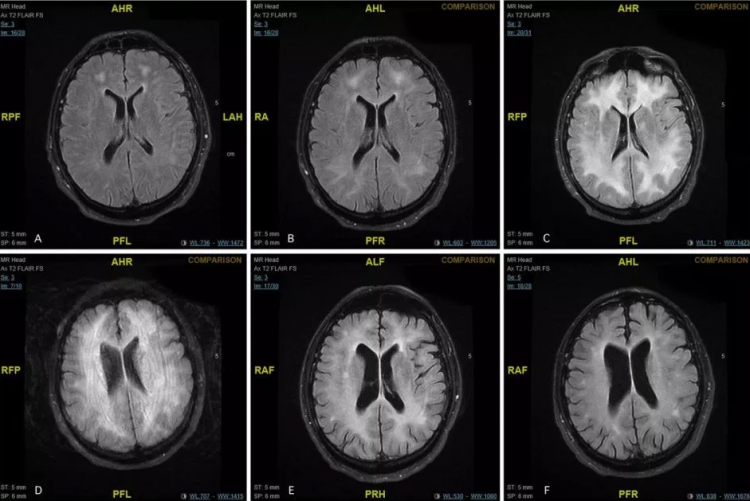

MRI scans revealed damage to the white matter in the brain. “It may present in several different ways,” said Dr. Abdilla.

They treated a 45-year-old man who was rushed by his parents to hospital in Malta. The patient was confused before doctors realized he was suffering from cocaine-induced toxic leukoencephalopathy.

Doctors treated him and he was transferred to a rehab facility. After four months, he was already walking on his own and showed signs of improvements.